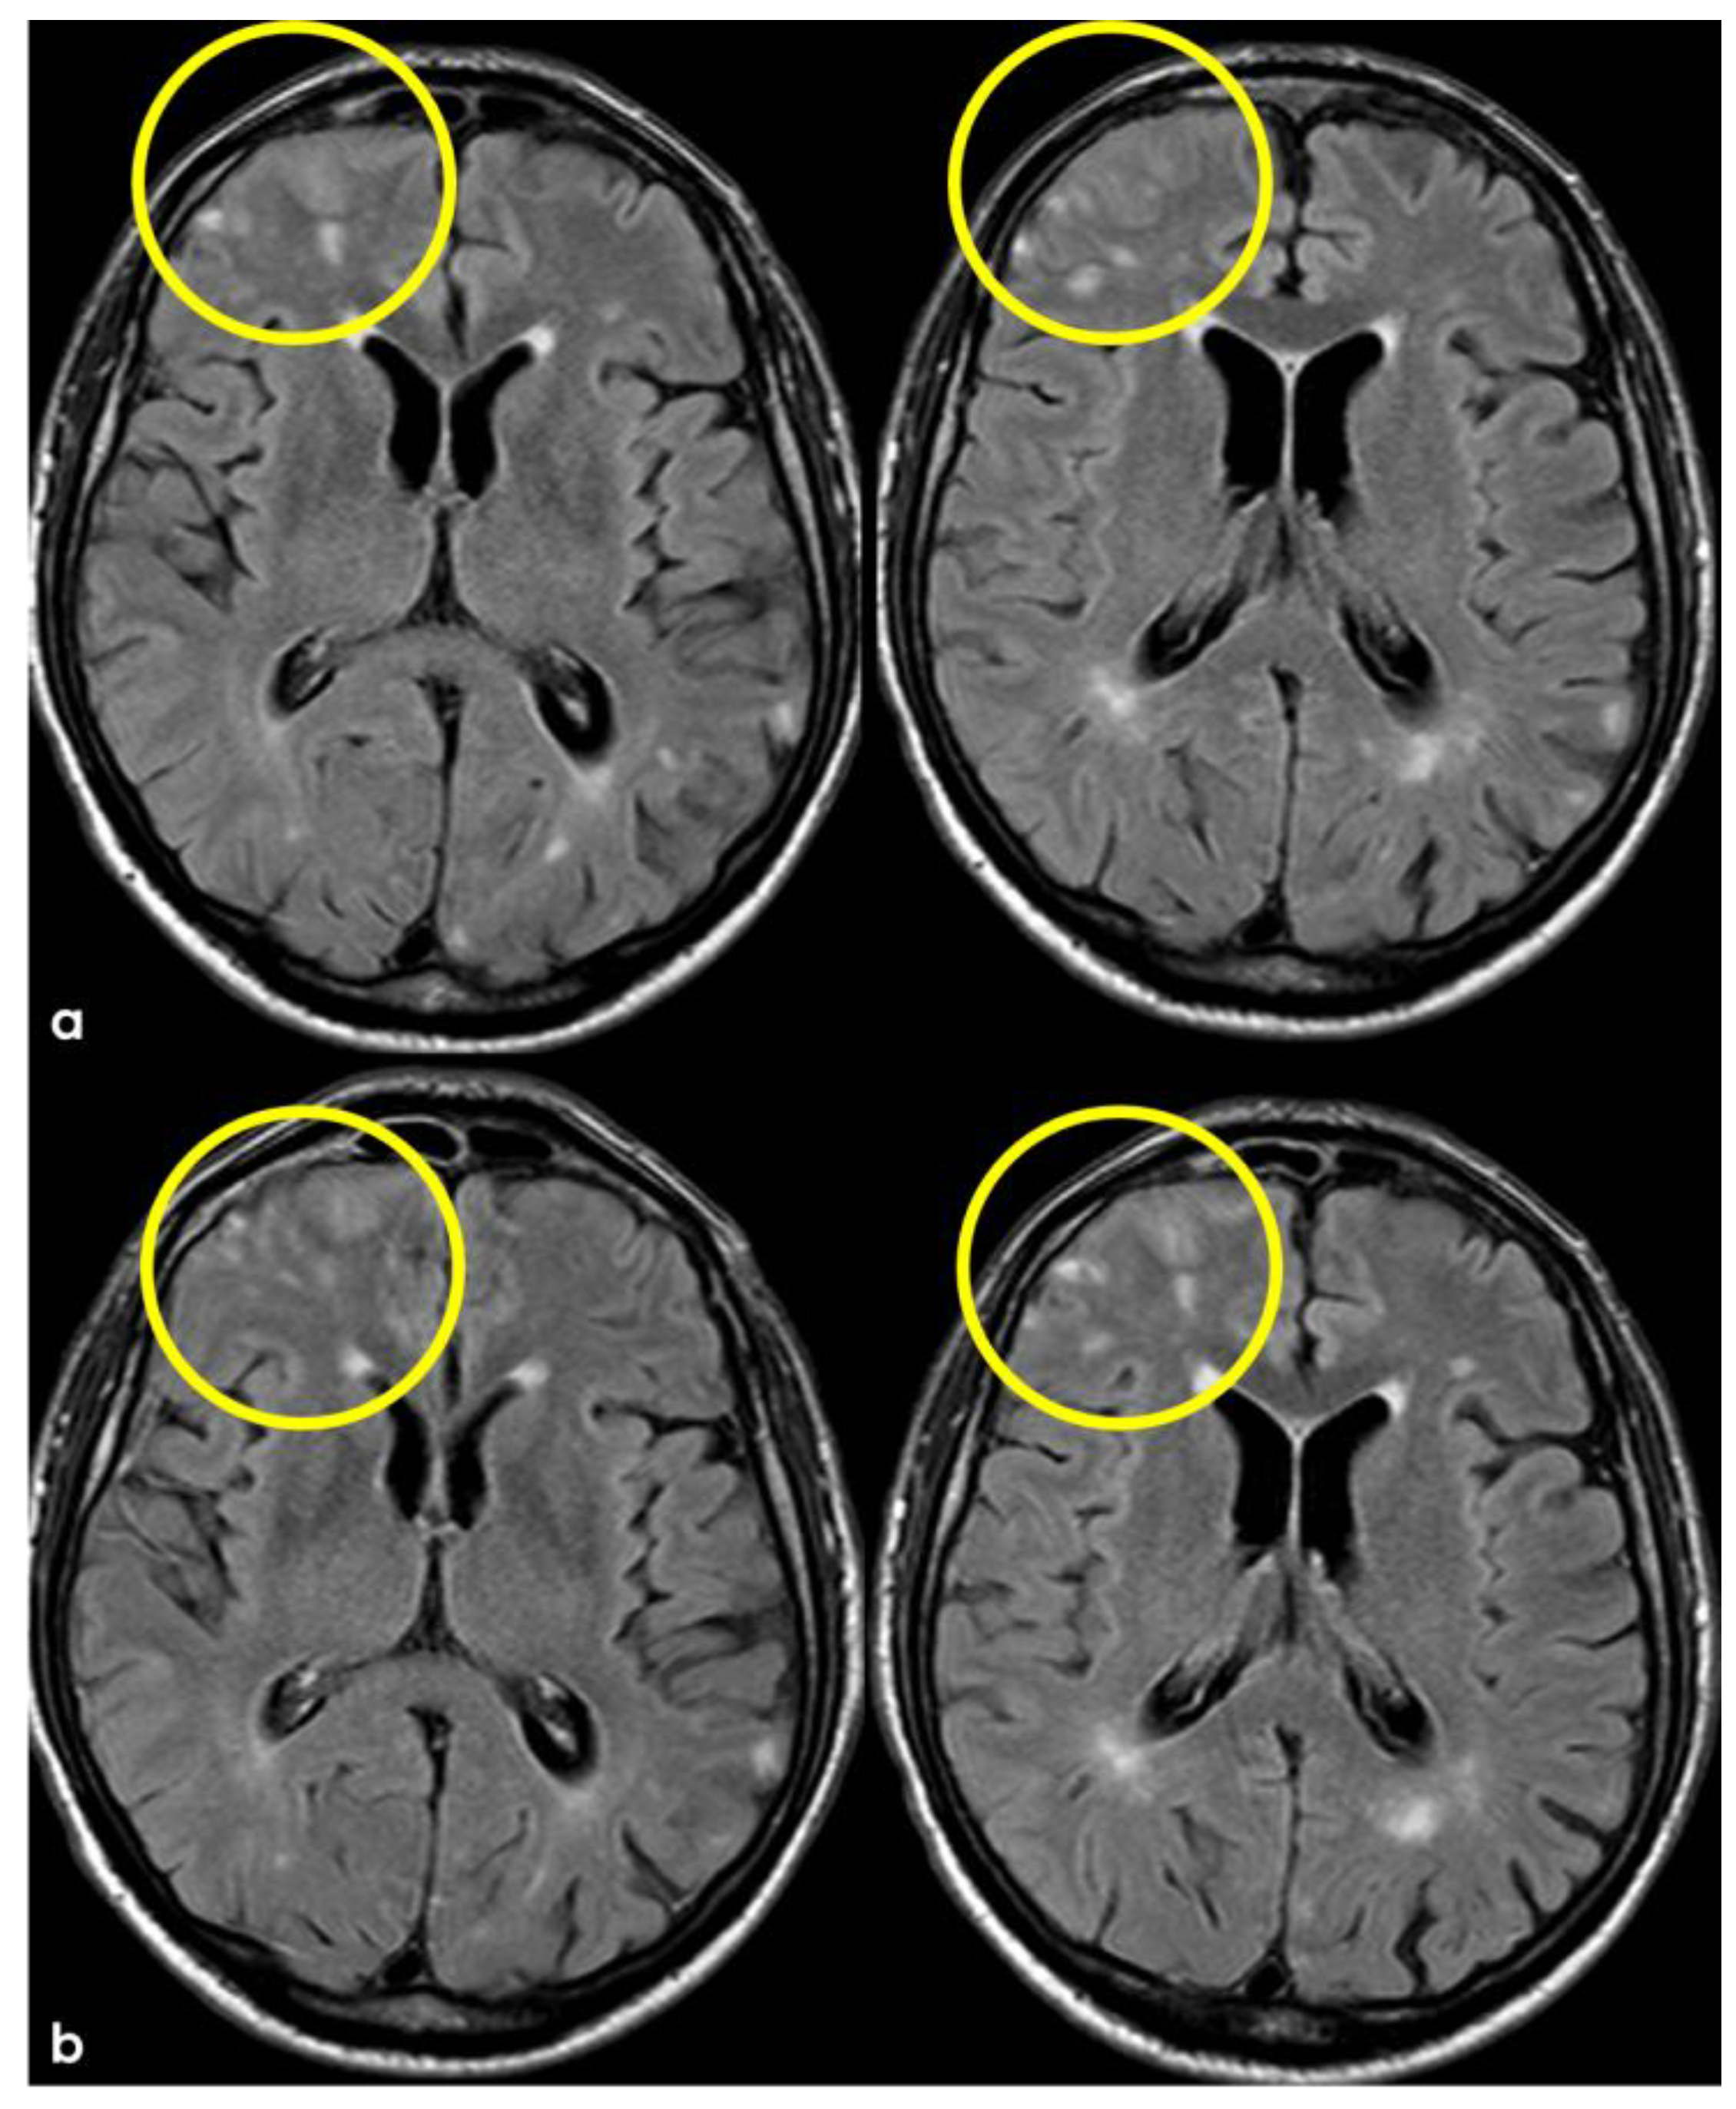

3. May 2014: CAA-Related Inflammation

5. February 2017: First Recurrent CAA-Related Inflammation

7. April 2018: Second Recurrent CAA-Related Inflammation

8. April 2018: Third Recurrent CAA-Related Inflammation